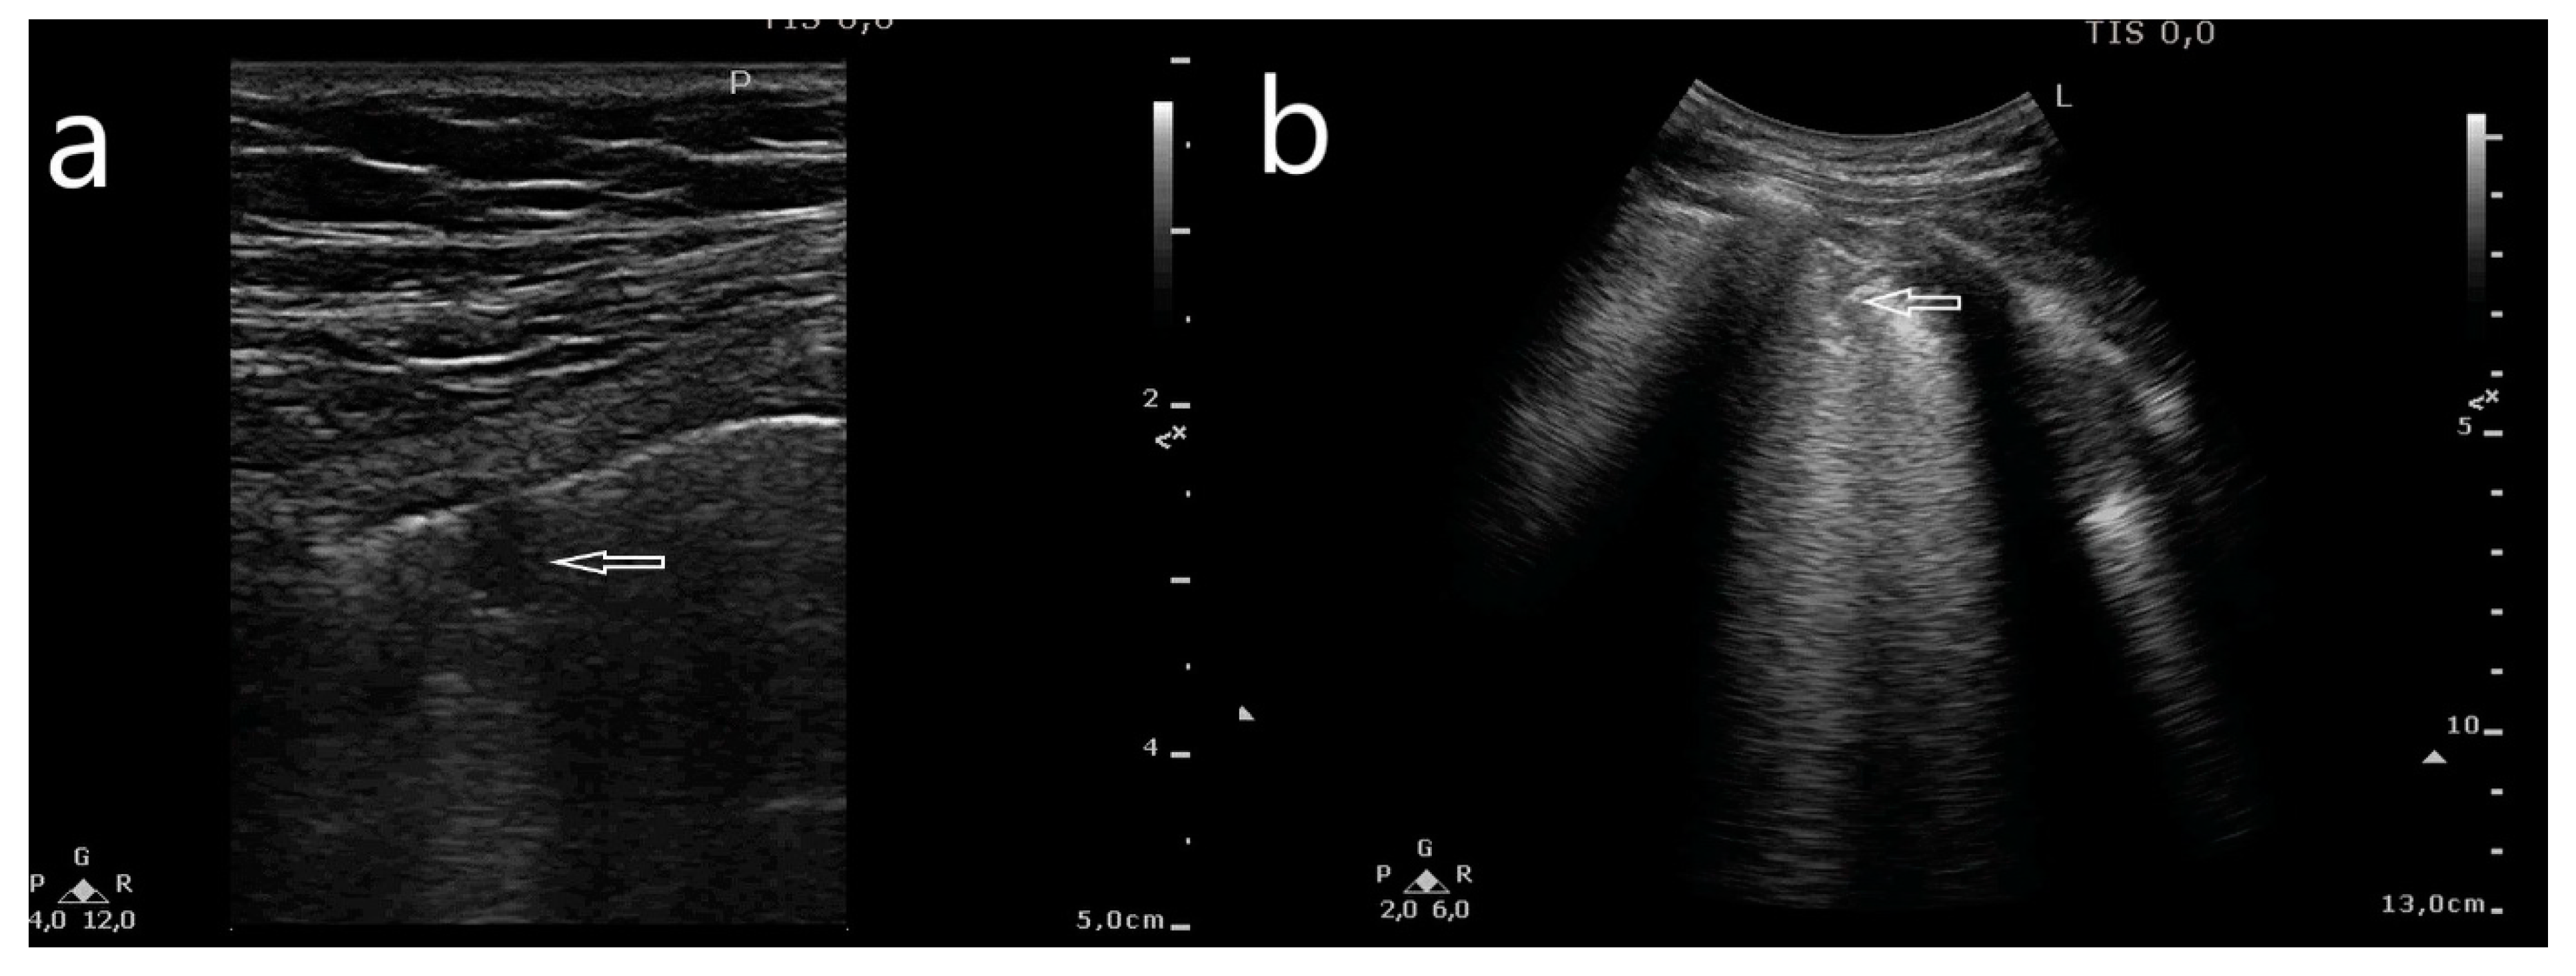

- Consolidations: small subpleural consolidations (up to 5 mm) accompanied with C-line artifacts, large consolidations involving segments and/or lobes, pleural effusion.

- Small subpleural consolidations (up to 5 mm) accompanied with C-line artifacts;

- Large consolidations involving segments and/or lobes;

- Small subpleural consolidations in an HRCT scan and small subpleural consolidations in an LUS image (p = 0.006), and single but multifocal B-line artifacts (p = 0.001).

- Large consolidations involving segments or lobes in an HRCT scan and large consolidations in an LUS image (p = 0.007).